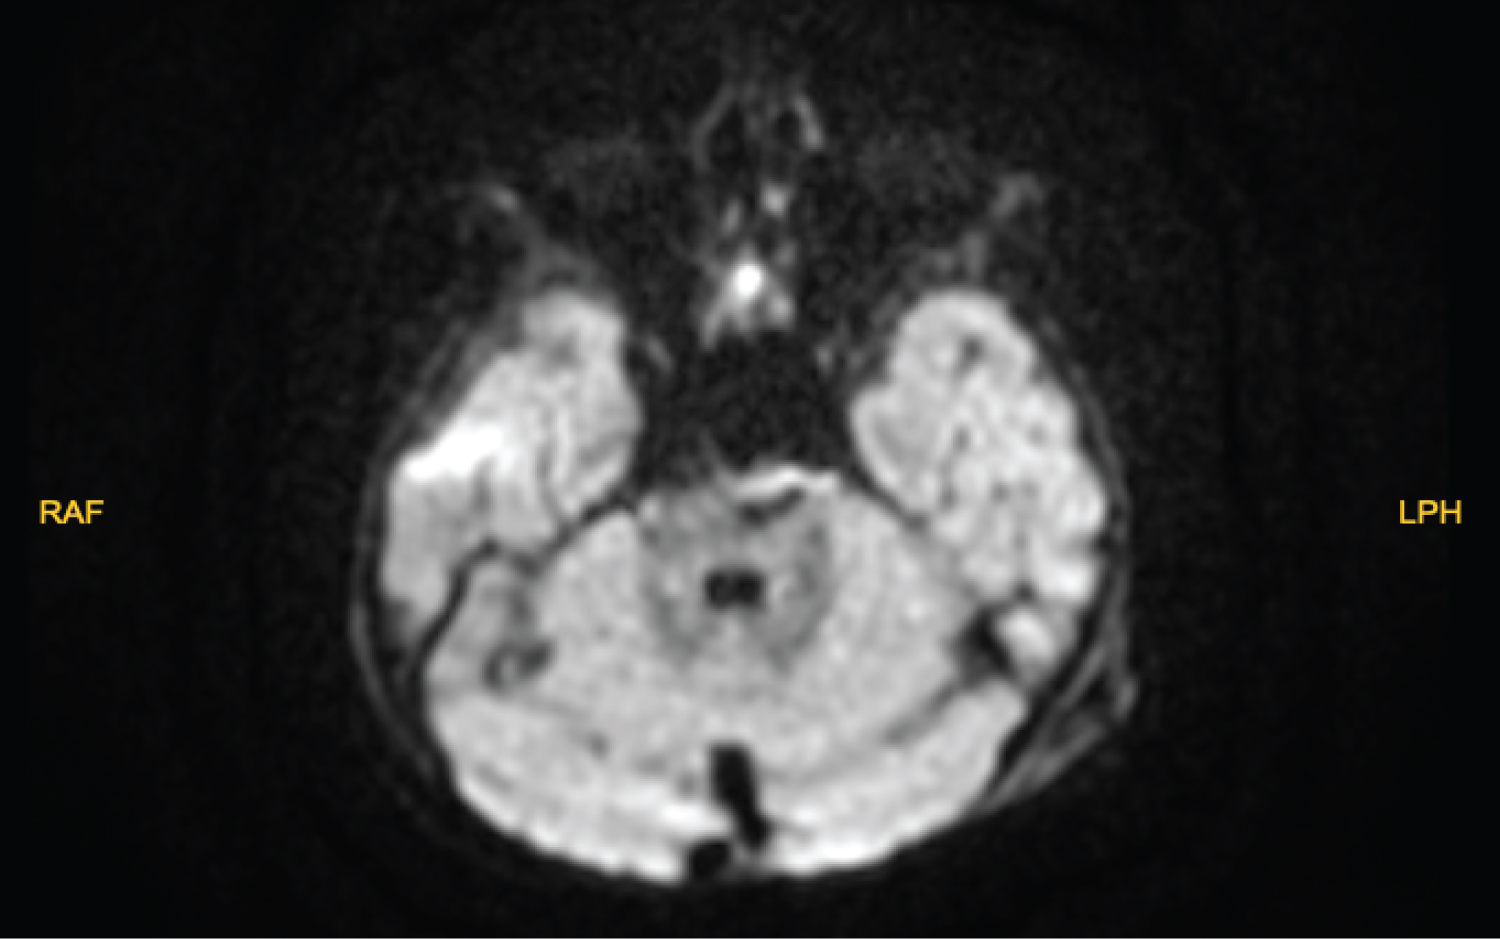

Blood tests were evaluated, and no pathologic value was seen. Magnetic resonance imaging (MRI) and angiography (MRA) was obtained which revealed a pontin mass along the dorsal aspect of the posterior fossa. The lesion is heterogeneously hyperintense on T1 and T2 weighted sequences (Figure 1 and Figure 2). The mass was well-circumscribed and heterogeneous, and evidence of previous hemorrhage within it. He was consulted to our department with preliminary diagnosis of pontine cavernoma and hemangioma. The differential diagnoses of an intracranial vascular lesion in this one year-day old infant included hemangioma, hemangioblastoma, vascular malformation, and other neonatal tumor types, such as soft-tissue sarcoma [8].

Figure 2: Diffusion sequence of the lesion. View Figure 2